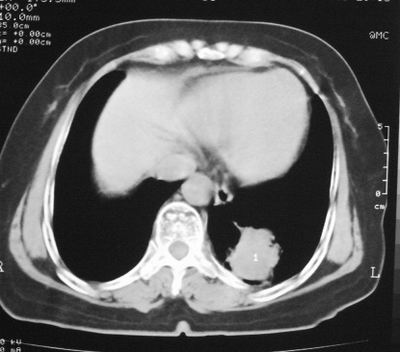

患者,女,64岁,4年前左腮腺"多形性"腺瘤手术治疗史.现复查胸部ct见左下肺块状影,该影与原左腮腺手术是否有联系?

本次复查胸部ct

左下肺后基底段实性肿块,周围有毛刺,病变周围有肺气肿,与降主动脉间有条带状影相连,病灶4年前查体发现,纵隔内未见肿大淋巴结。考虑.肺隔离症,建议增强扫描与周围型肺癌鉴别。